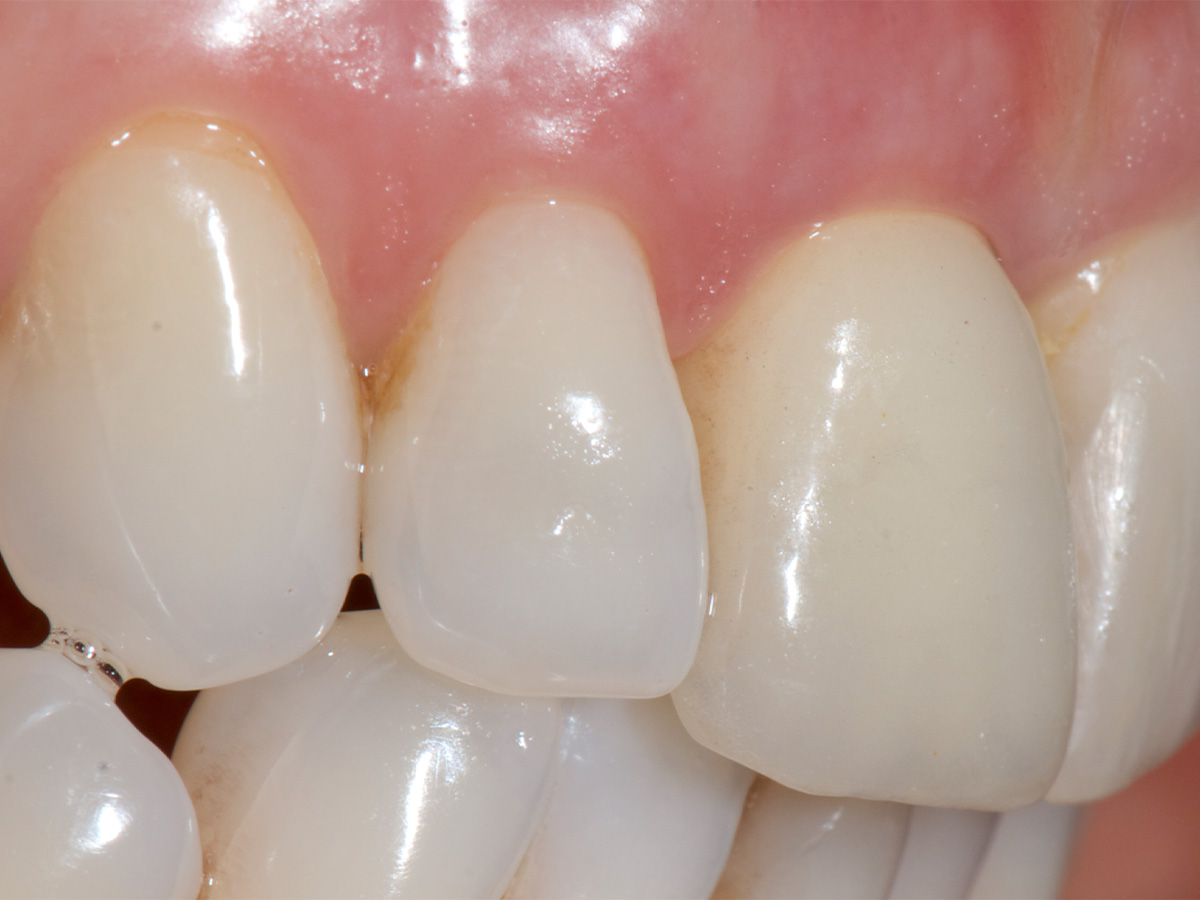

Der Zahntechniker übertrug die Implantatposition auf das Meistermodell und fertigte am selben Tag das definitive Abutment mit dem idealen Emergenzprofil und eine provisorische Krone an. So konnte der Patient direkt mit dem definitiven Abutment versorgt werden. Nach einer Einheilphase von drei Monaten wurde zur Stabilität der peri - implantären Weichgewebsarchitektur das Gewebe verdickt. Eine sehr gute Technik dafür ist die Entnahme eines entepithelialisierten Transplantats aus der Tuberregion. Dies wurde mit der Tunneltechnik eingebracht und mit Nähten fixiert. Die definitive Versorgung des Implantats erfolgte nach einer Einheilzeit von acht Wochen. Im finalen Bild lässt sich gut erkennen, dass das Volumen erhalten werden konnte.

Definitive Versorgung.Trotz des großen Defekts ließ sich ein sehr gutes Ergebnis erzielen.

Trotz des großen Defekts ließ sich in diesem Fall ein sehr gutes Ergebnis erzielen. Durch die Bone-Lamina-Technik kann bei der Sofortimplantation die vestibuläre knöcherne Wand verstärkt oder sogar wieder hergestellt werden. Die Technik ermöglicht eine biologische Regeneration von vitalem Knochen. Somit kann das Volumen der Alveole erhalten werden. Dieses präventive einzeitige Vorgehen ermöglicht es, in der Front eine ideale Ausgangssituation für den Langzeiterfolg und die Ästhetik zu schaffen. Um den Erfolg und die Stabilität des Behandlungsergebnisses dieser Methode nach Jahren bestätigen zu können, sind weitere Langzeitstudien abzuwarten.